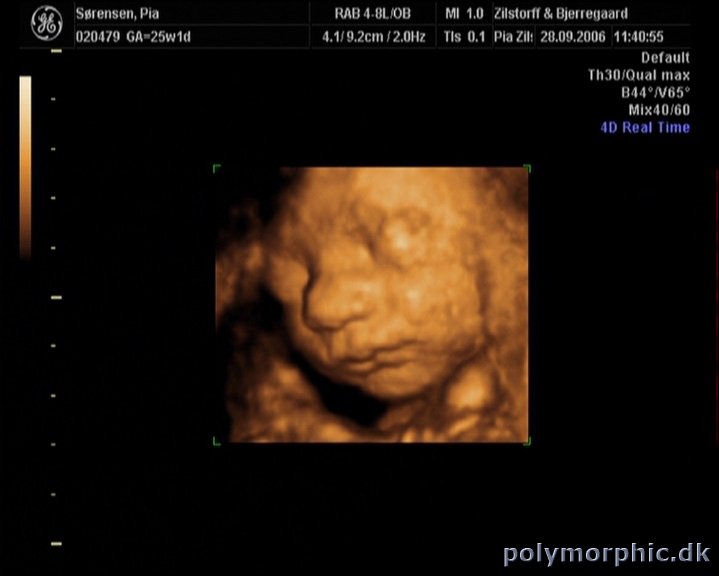

3D scanning

I går var vi til 3D scanning i århus hos Zilstorff & Bjerregaard. Sikke en oplevelse! Vi fik nogle rigtigt gode billeder med hjem og en dvd med optagelse fra selve scanningen.